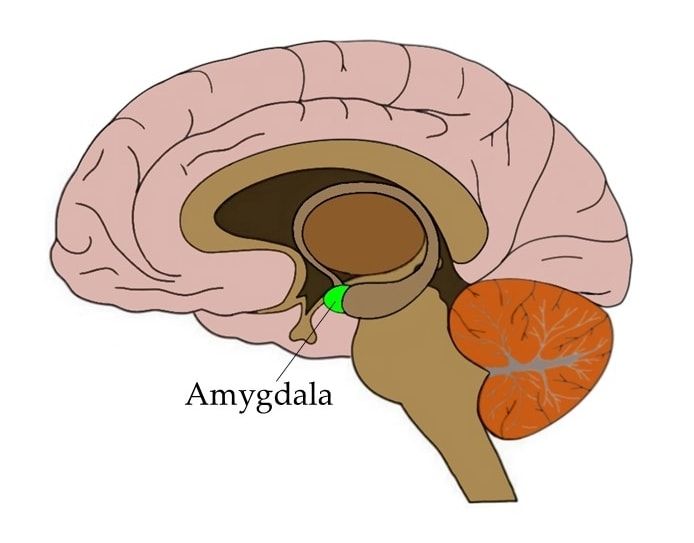

Amygdala: What It Is and What It Controls

Know Your Brain: Amygdala

Amygdala Function and Location

Amygdala's Location and Function

Amygdala: Anatomy, Location, and Function

Where in the brain is the amygdala located? - Quora